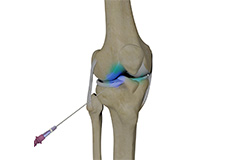

Platelet-Rich Plasma (PRP) Injections for the Knee

Platelet-rich plasma (PRP) injections for the knee are a minimally invasive treatment designed to reduce pain, improve joint function, and potentially promote healing in knee injuries or degenerative conditions.

Viscosupplementation

Viscosupplementation refers to the injection of a hyaluronan preparation into the joint. Hyaluronan is a natural substance present in the joint fluid that assists in lubrication. It allows the smooth movement of the cartilage-covered articulating surfaces of the joint.

Intra-articular Knee Injection

Knee pain and stiffness can be disabling and difficult to treat. It can limit an individual’s lifestyle and negatively impact body image and emotional well-being.